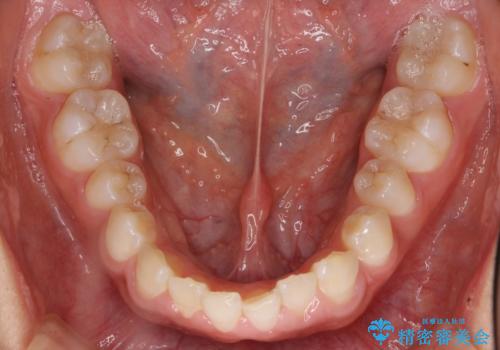

前歯のすきま 矯正治療とセラミックで小さな歯を形良く

- 前歯のすきまを気にして来院。

左上の2番が生まれつき小さく、スペースが余っていました。

右上の2番もやや小さめでしたが、相談の上、左上2番のみセラミックで形を整えることとしました。

そのほかの隙間はマウスピース矯正で閉じることにしました。